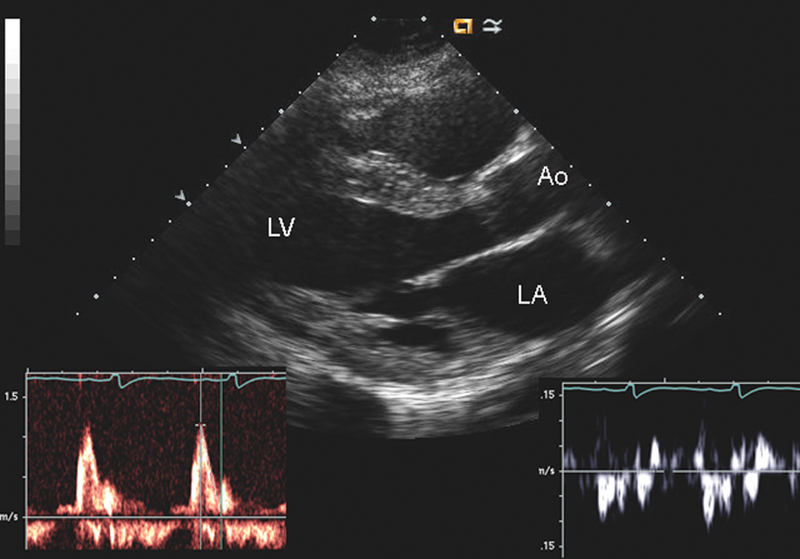

فحوصات تشخيصية لبعض امراض القلب والشرايين التاجية